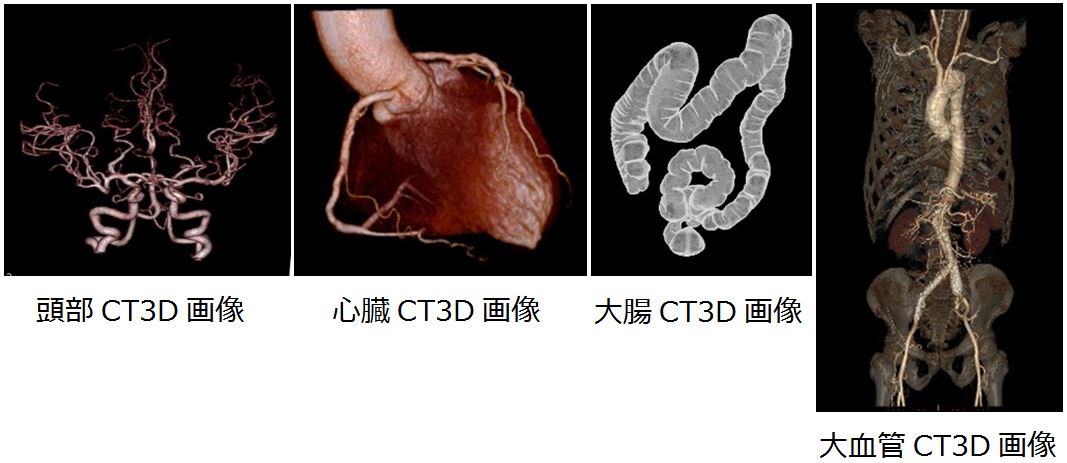

CT 検査︓Computed Tomography(コンピューター断層撮影)

CT検査には単純CT検査と造影剤を使⽤して⾏う造影CT検査があります。

当院のCT検査は、X線CT認定技師の認定を受けた診療放射線技師を中⼼とし、精度管理のもと安全に⼼掛けて検査を⾏っています。

●造影CT検査について

- 検査前は絶⾷です。(⽔分は摂取して下さい)

- 静脈から造影剤を注⼊し検査を⾏います。

●CT検査の準備、検査開始、検査中について

- ⾦属類(ネックレスなどの貴⾦属や下着の⾦具など)を⾝に着けていると撮影に影響する場合があるため、検査前に外して頂きます。

- CT 検査は検査寝台に寝て⾏い、検査時間は単純CT検査で約5分、造影CT検査で約10〜30分程です。

- 検査開始後は、体を動かさないようにして下さい。

- 気分が悪くなったり、いつもと違うと感じたら直ぐにスタッフにお知らせ下さい。

- 検査後は⾷事も可能となり、普段通りの⽣活を送って下さい。